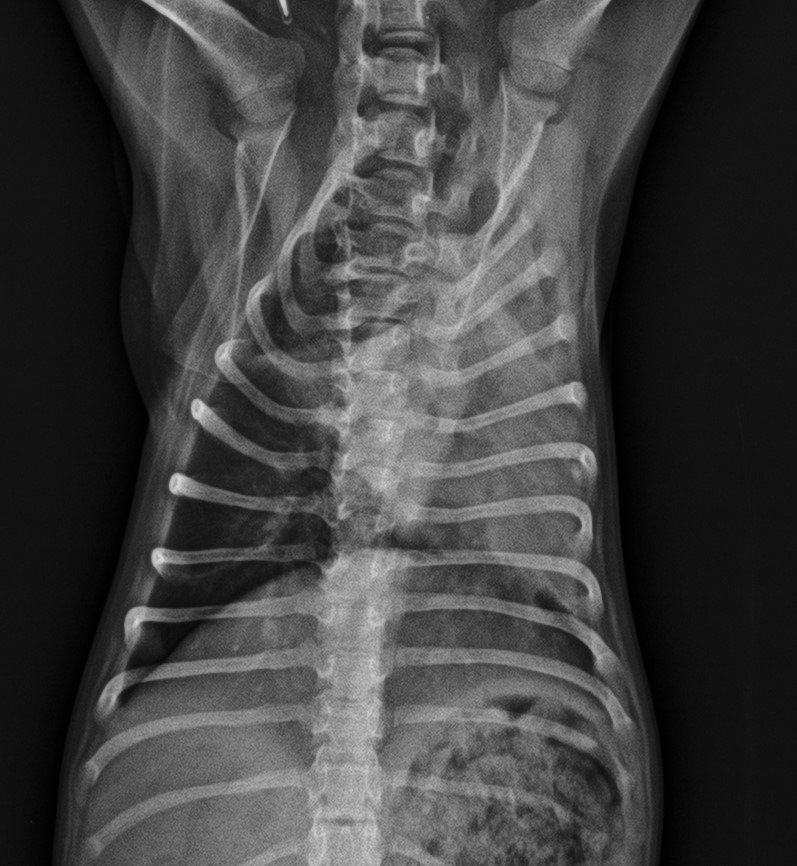

Sienna padece hidrocefalia, una condición muy delicada que pone en riesgo su vida. Fue vendida por un criador y, poco después, sus anteriores tutores nos la trajeron en medio de una crisis convulsiva muy grave. Además, como consecuencia de esas convulsiones, desarrolló una neumonía por aspiración severa que actualmente estamos tratando en la clínica donde trabajo.